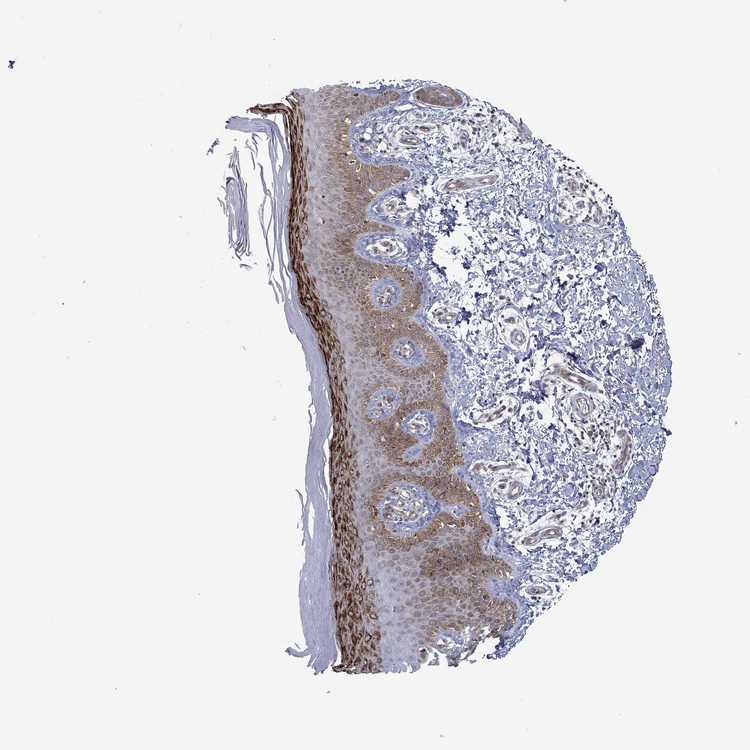

TISSUE PRIMARY DATA SKIN Show tissue menu

SKIN 1 - Antibody stainingi

Antibody staining in the annotated cell types in the current human tissue is reported as not detected, low, medium, or high, based on conventional immunohistochemistry profiling in selected tissues. This score is based on the combination of the staining intensity and fraction of stained cells.

Each image is clickable and will lead to virtual microscopy that enables deeper exploration of all samples and also displays staining intensity scores, fraction scores and subcellular localization as well as patient and tissue information for each sample.

Antibody HPA018246Antibody HPA055475

Langerhans Not detectedNot detected

Fibroblasts Not detectedNot detected

Keratinocytes HighNot detected

Melanocytes LowMedium

SKIN 2 - Antibody stainingi

Epidermal cells HighMedium